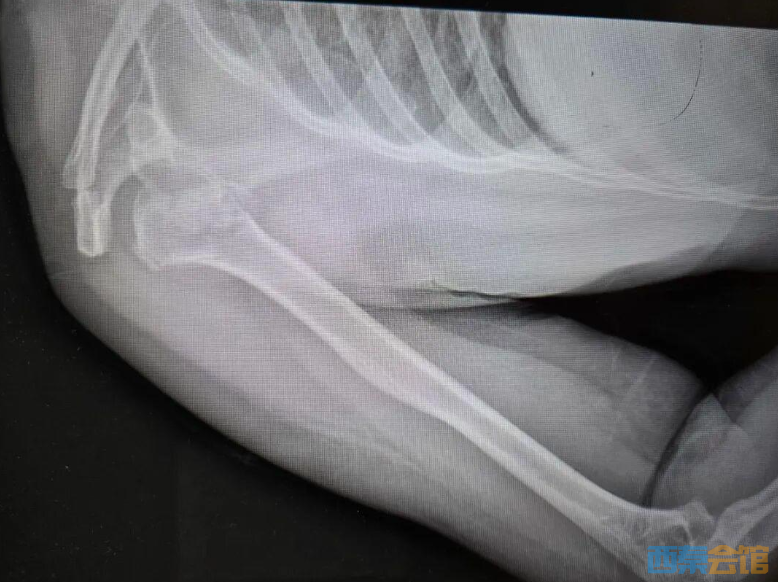

送医后的CT检查结果显示:右肱骨近端四部分粉碎性骨折,且伴有罕见的肱骨头后脱位。她的肩膀碎成了七八块,而且关节位置发生了严重偏移。由于手术难度极大,她被紧急转诊至河南省人民医院。

“我第一反应是不相信!没喝酒、没摔下床,就在被窝里躺着,肩膀怎么可能碎成这样?”负责接诊的创伤骨科刘涛主任直言,这是他从业多年见过最蹊跷的病例之一。

经过数小时的精细操作,医生像“捞针”一样把掉进关节深处的碎骨块一一复位、加固。手术成功了,但一个问号依然悬在医生心头:那股震碎骨头的暴力,到底从哪来?

在排除了肿瘤破坏骨质、严重骨质疏松后,刘涛主任盯住了一个细节——肩关节后脱位。

“肩关节后脱位相当罕见,在所有肩关节脱位中不到4%,而它最常见的诱因就是癫痫发作。”刘涛主任解释道,“前脱位很常见,但后脱位需要非常大的暴力才能造成。”